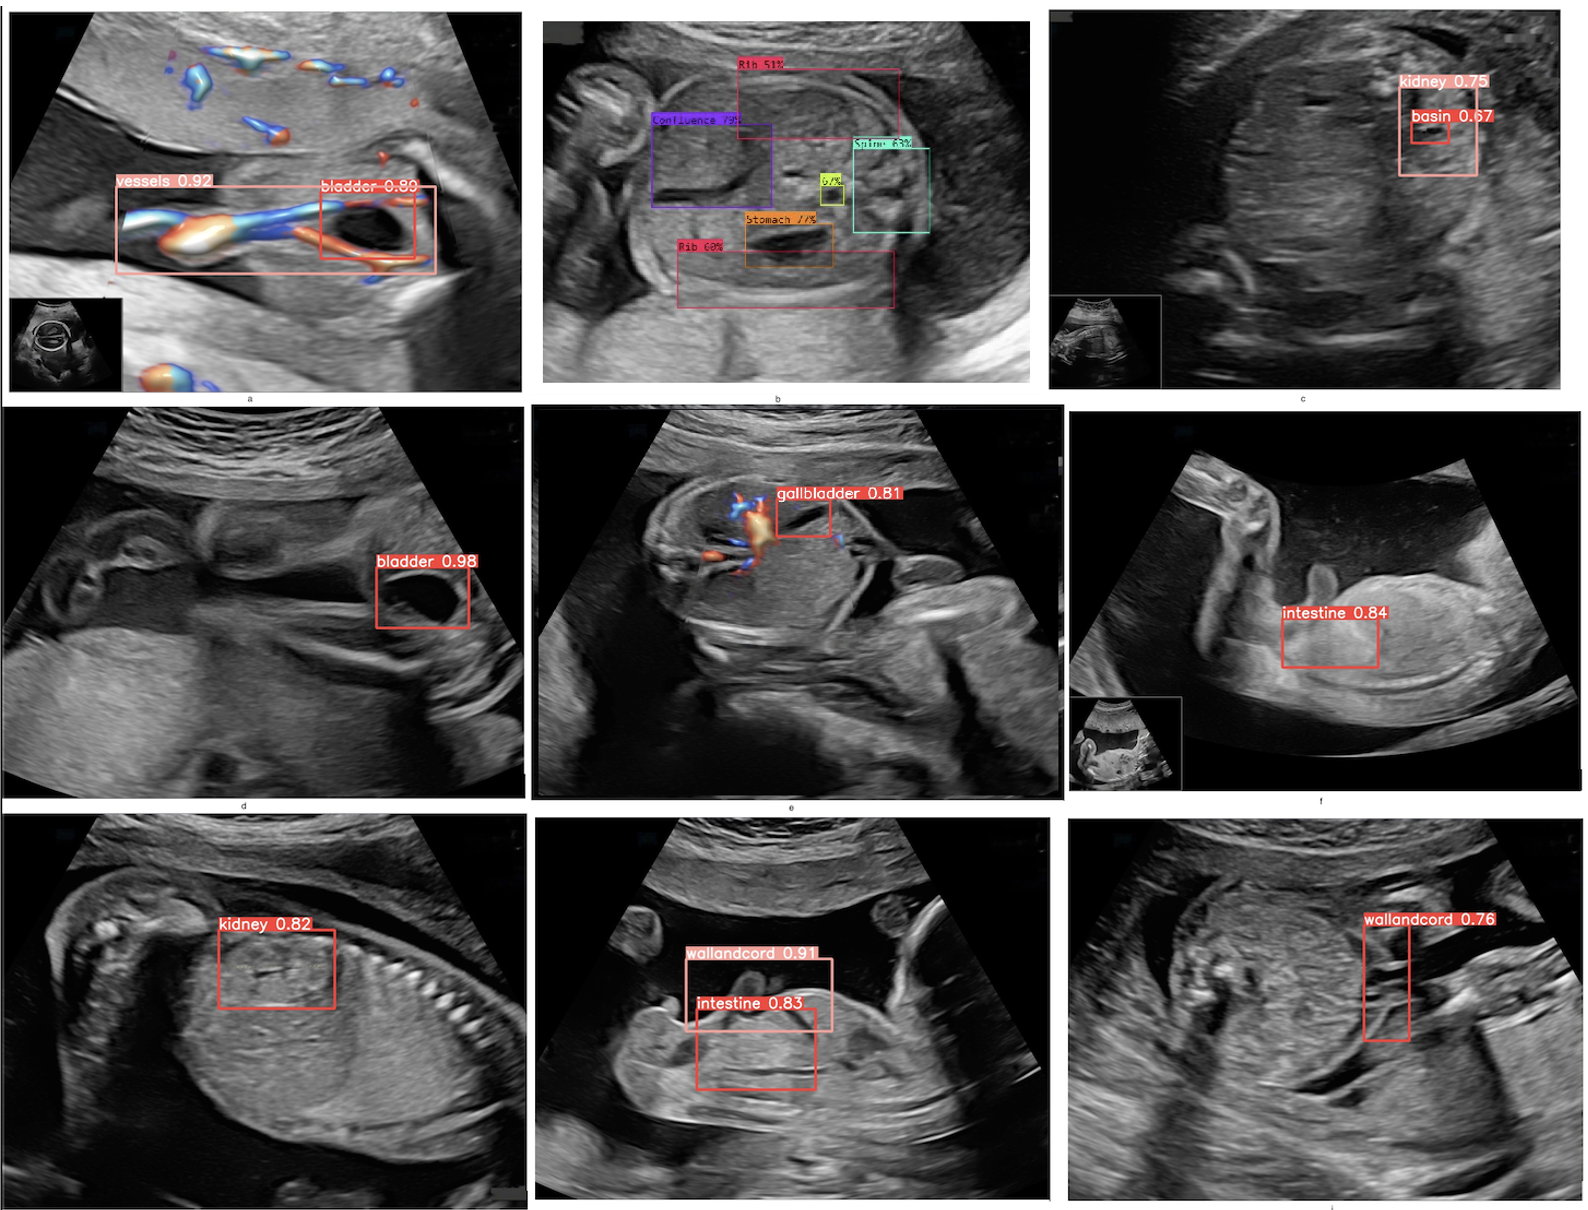

Exemple de capturi de ecran dintr-o ecografie morfologică fetală, ilustrând modul în care

sistemul de inteligență artificială detectează organele anatomice și planurile biometrice, fiecare zonă fiind

încadrată și etichetată cu probabilitatea asociată recunoașterii (ex. vezică urinară, rinichi, intestin, cordon ombilical).